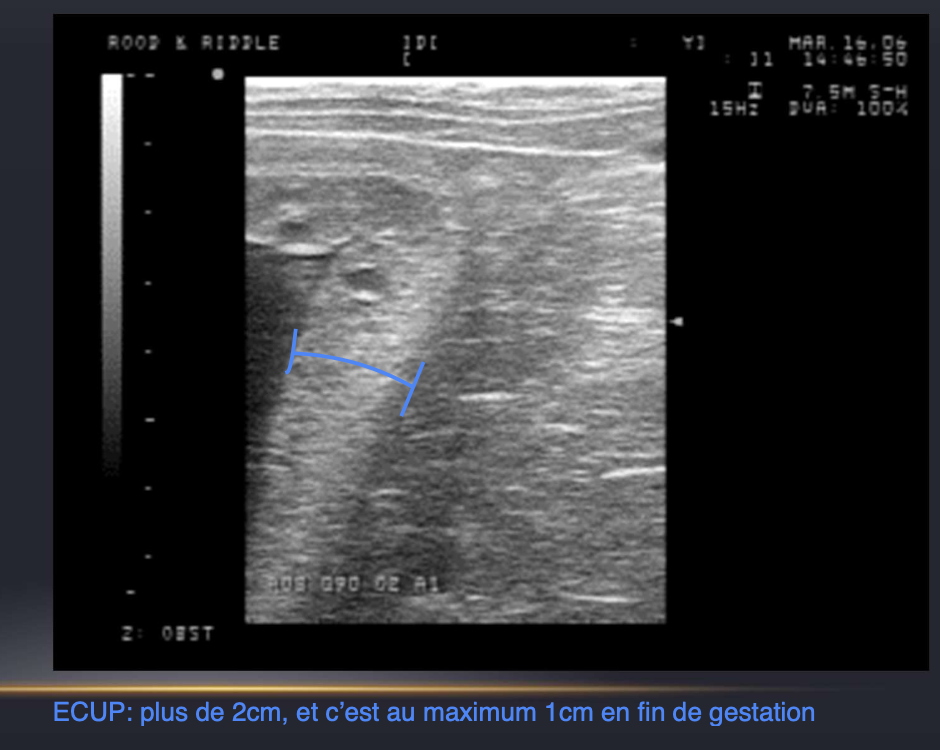

Quels sont les éléments observés à l’echographie lors du diagnostic des placentites (4)

• ECUP (epaisseur combinée uterus-placenta)

Quelle est l’épaisseur normale de l’uterus-placenta (ECUP) ***EXAM

Age de gestation-1